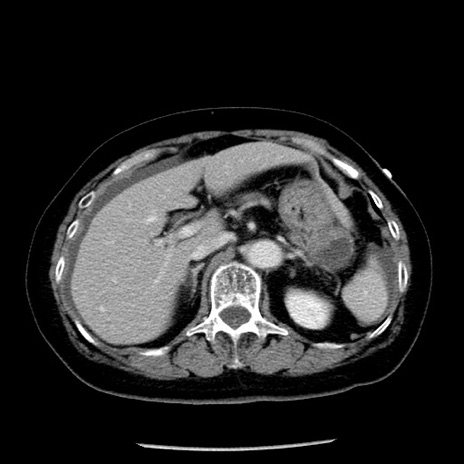

症例13(横断像)

【症例】70歳代女性

【主訴】腹痛、嘔吐

【現病歴】15時間程前(昨晩)より腹痛あり。今朝になっても症状の改善なく、嘔吐あり。腹痛も増悪あり、救急外来受診。

【既往歴】子宮癌全摘術後

【身体所見】意識清明、BP 121/72mmHg、P 74bpm、SpO2 100%(RA)、腹部:平坦・軟、腸雑音ほぼ聴取せず。下腹部・心窩部・臍左上に圧痛あり。反跳痛なし。

【データ】WBC 10600、CRP 0.15